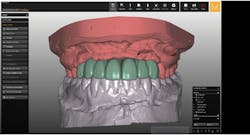

A cone beam computed tomography (CT) scan (Prexion 3-D cone beam unit, Prexion Inc.) of the upper jaw was obtained. A full-arch upper impression was taken in polyvinyl siloxane (PVS) and poured in model stone. Then a CT scan was taken of the model. Both sets of DICOM files were imported into Blue Sky Plan software (Blue Sky Bio LLC), where all digital planning occurred. Using the “add tooth” function, digital teeth were added into the DICOM files. These were overlaid on the digitized model, and all aspects (midline, horizontal plane, bite, and overjet) were checked using basic principles of implant restorability (figure 2). This was done to ensure proper placement for future implant workup. Based on the available bone, there was room for five implants (3.5 mm x 10.5 mm MegaGen AnyRidge implants): a single implant for No. 5 and implants in Nos. 6, 8, 9, and 11 for two three-unit bridges. Even though there was marked bone loss, angulations were adjusted as much as possible to allow for implants to emerge through the lingual of the incisor (figure 3). Once the correct orientation was complete, we designed a fully guided surgical kit to print one guide for all drills. Guides were exported as STL files and 3-D printed using an in-office CEL Robox 3-D printer out of nGen material (ColorFabb BV). After printing the guide, we added a metal sleeve housing (figure 4).

Figure 2: Digital workup in Blue Sky Plan software